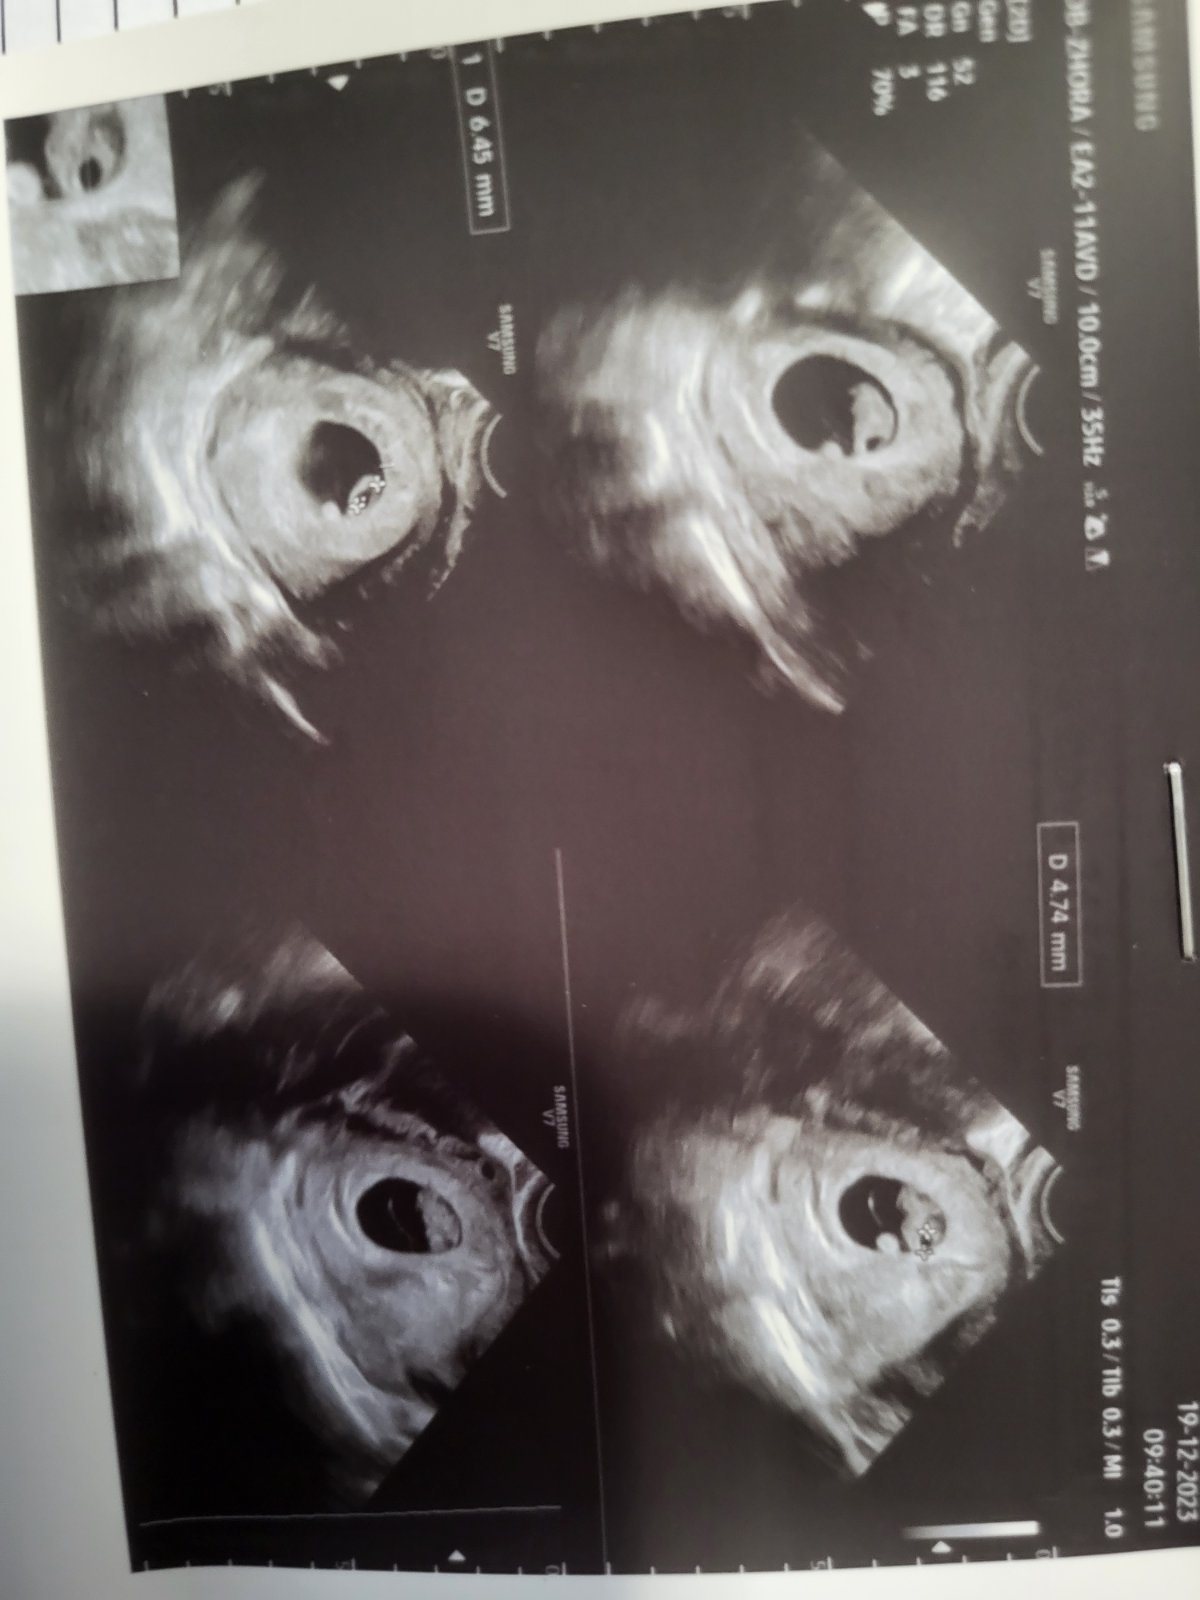

Sono v 8. týždni: Riziko tekutiny v hlavičke bábätka?

@lenik888 ahoj, odpisujem dosť neskoro. :D nakoniec tá tekutina ok,akurát so srdiečkom nám zistili problémy na sone v Martine , ale malý je úžasný 🤗